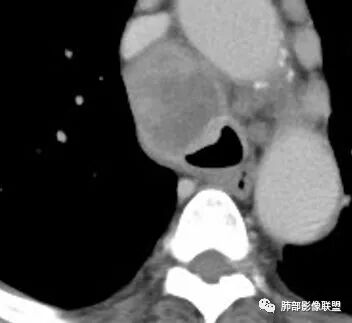

南边:临床:老年男性,病史偏长,2月。临床有通气功能障碍。

我们看影像,肺内有一些小斑点状高密度影,部分区域有气体潴留:

南边:我们现在影像上看的,也就是肺部小斑点,这些斑点,有些地方有气道储留的一个特点。

南边:但是我们看纵隔就多发的肿大淋巴结,部分融合成团。

南边:而且这些淋巴结,有些直接主要是压迫支气管壁,但是有些是突入到支气管腔内的。可惜我截的图发不上来。就左上舌段,支气管壁明显的增厚。有些明显腔内突的一个结节的,但是远的没有阻塞的特点。南边:增强以后呢,这个病灶明显强化,部分的似乎有环形强化的迹象,但不是很典型。

我们看这个主支气管的层面,主支气管明显受压,有变形的,但是软骨是没有突破的。

南边:那也就是说,这个纵隔淋巴结,它是没有影响到我们主支气管内部去的,周围有,可惜的膜部的增厚,我总心里不踏实,后面因为食道贴在一起啦。 因此这些淋巴结在主支气管层面是没有影响的。